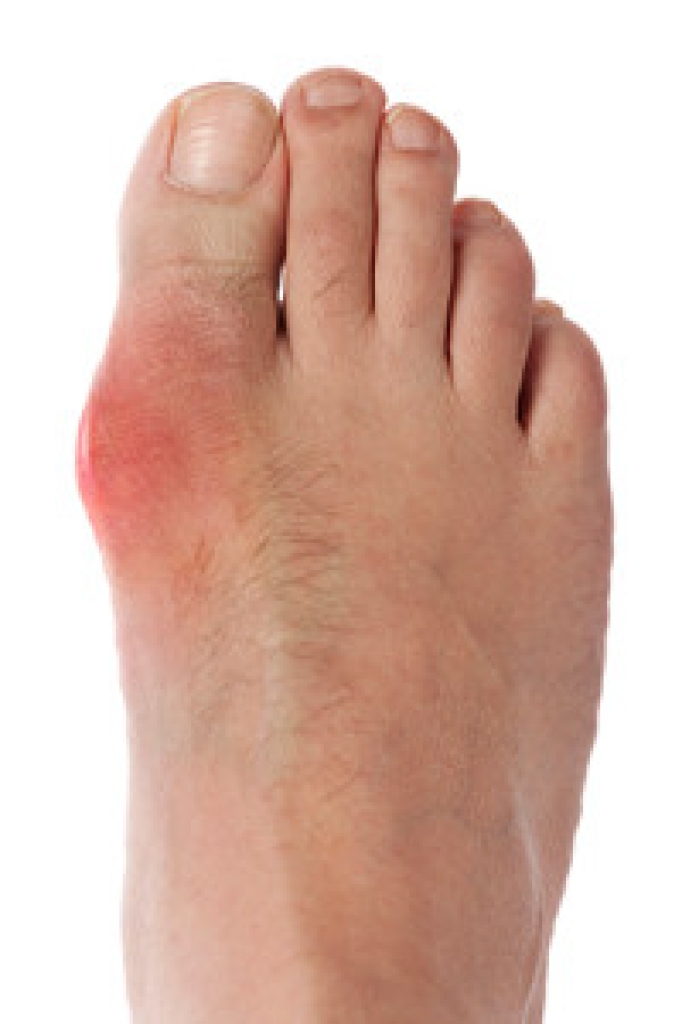

The pain associated with spurs is often because of weight placed on the feet. When someone is walking, their entire weight is concentrated on the feet. Bone spurs then have the tendency to affect other bones and tissues around the foot. As the pain continues, the feet will become tender and sensitive over time.